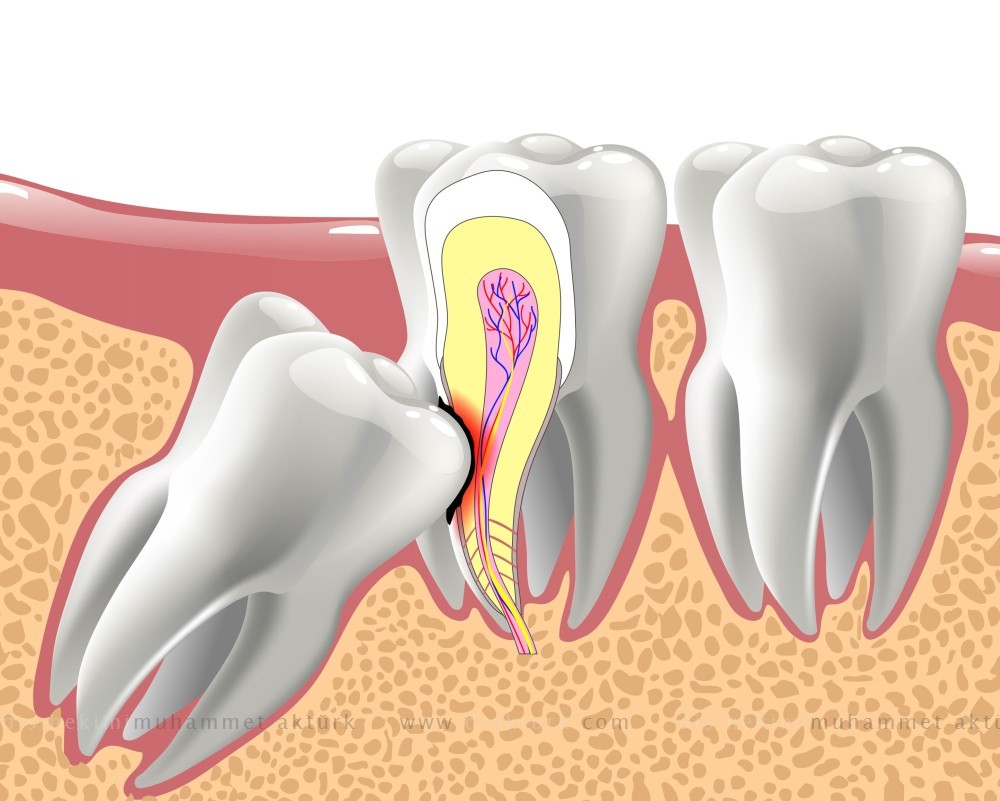

ينمو للعديد من الأفراد ضروس عقل متأثرة — ضروس لا يوجد لها متسع كافي لتنبثق داخل الفم أو لتنمو بشكل طبيعي. قد لا تنبثق ضروس العقل المطمورة (الدفينة) إلا انبثاقًا جزئيًا، أو لا تنبثق على الإطلاق.

إن أضراس العقل المطمورة:

- قد تنمو في زاوية باتجاه الأسنان المجاورة (الضرس الثاني)

- قد تنمو في زاوية باتجاه الجزء الخلفي من الفم

- قد تنمو في الزاوية الصحيحة من الأسنان الأخرى كما لو كان ضرس العقل "ممددًا" داخل عظمة الفك

- قد تنمو بشكل مستقيم لأعلى أو لأسفل كباقي الضروس، ولكن تبقى حبيسة داخل عظم الفك